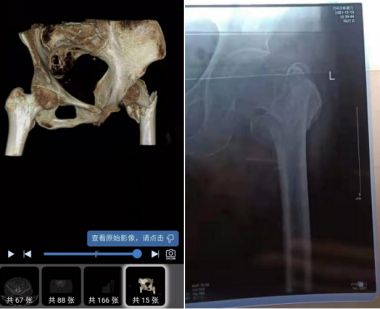

病例分享:

夏氏骨折丸,针对严重性骨折,粉粹性骨折,陈旧性骨折,严重性和粉粹性骨折40天康复,陈旧性60天康复!